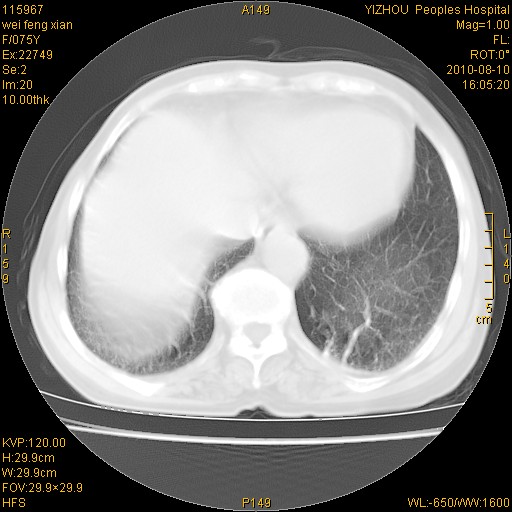

标题: CT28313:两肺弥漫性病变 [打印本页]

标题: CT28313:两肺弥漫性病变

女,75岁,患者反复头昏乏力面色苍白3年,再发10天入院。临床贫血查因。

考虑慢支伴右上肺慢性感染可能性大,建议结合临床排外尘肺可能。

考虑尘肺可能性大.

如果患者是男性首先考虑尘肺,但现在即是是女性也要询问职业病史。

考虑尘肺并结核;右上肺支气管扩张!

结核、尘肺、支气管肺泡癌都不能除外

考虑右肺上叶继发性肺结核伴两肺播散。